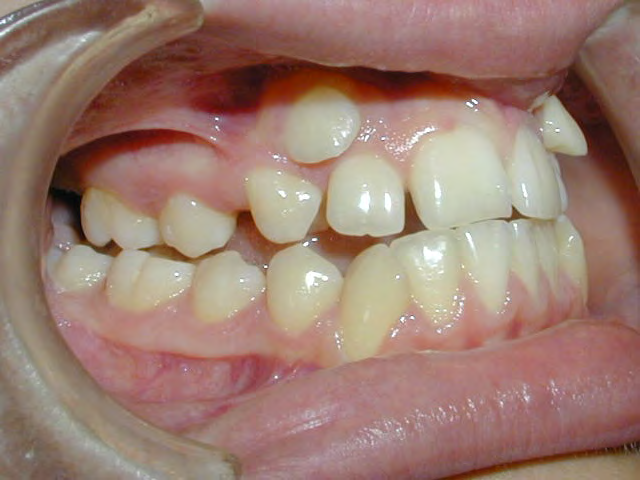

All of the patients below had been told they required extractions by orthodontists, some insisting that they could not be treated without extractions.

They were all treated without extractions, head gear or facemasks at Vakresmil and represent just a small sample of cases treated between 2004–2014.

Below are cases treated at Vakresmil without extractions within the last three years. The families had been told, “It is simply not possible for your child to be treated without extractions” by orthodontists. Judge for yourself if that was right or wrong.

The overall aim is to produce the best smile we can — a “beautiful smile”, if you will — without premolar extractions, headgear, facemasks or banded appliances. A smile that both the patient and we at Vakresmil can be proud of.